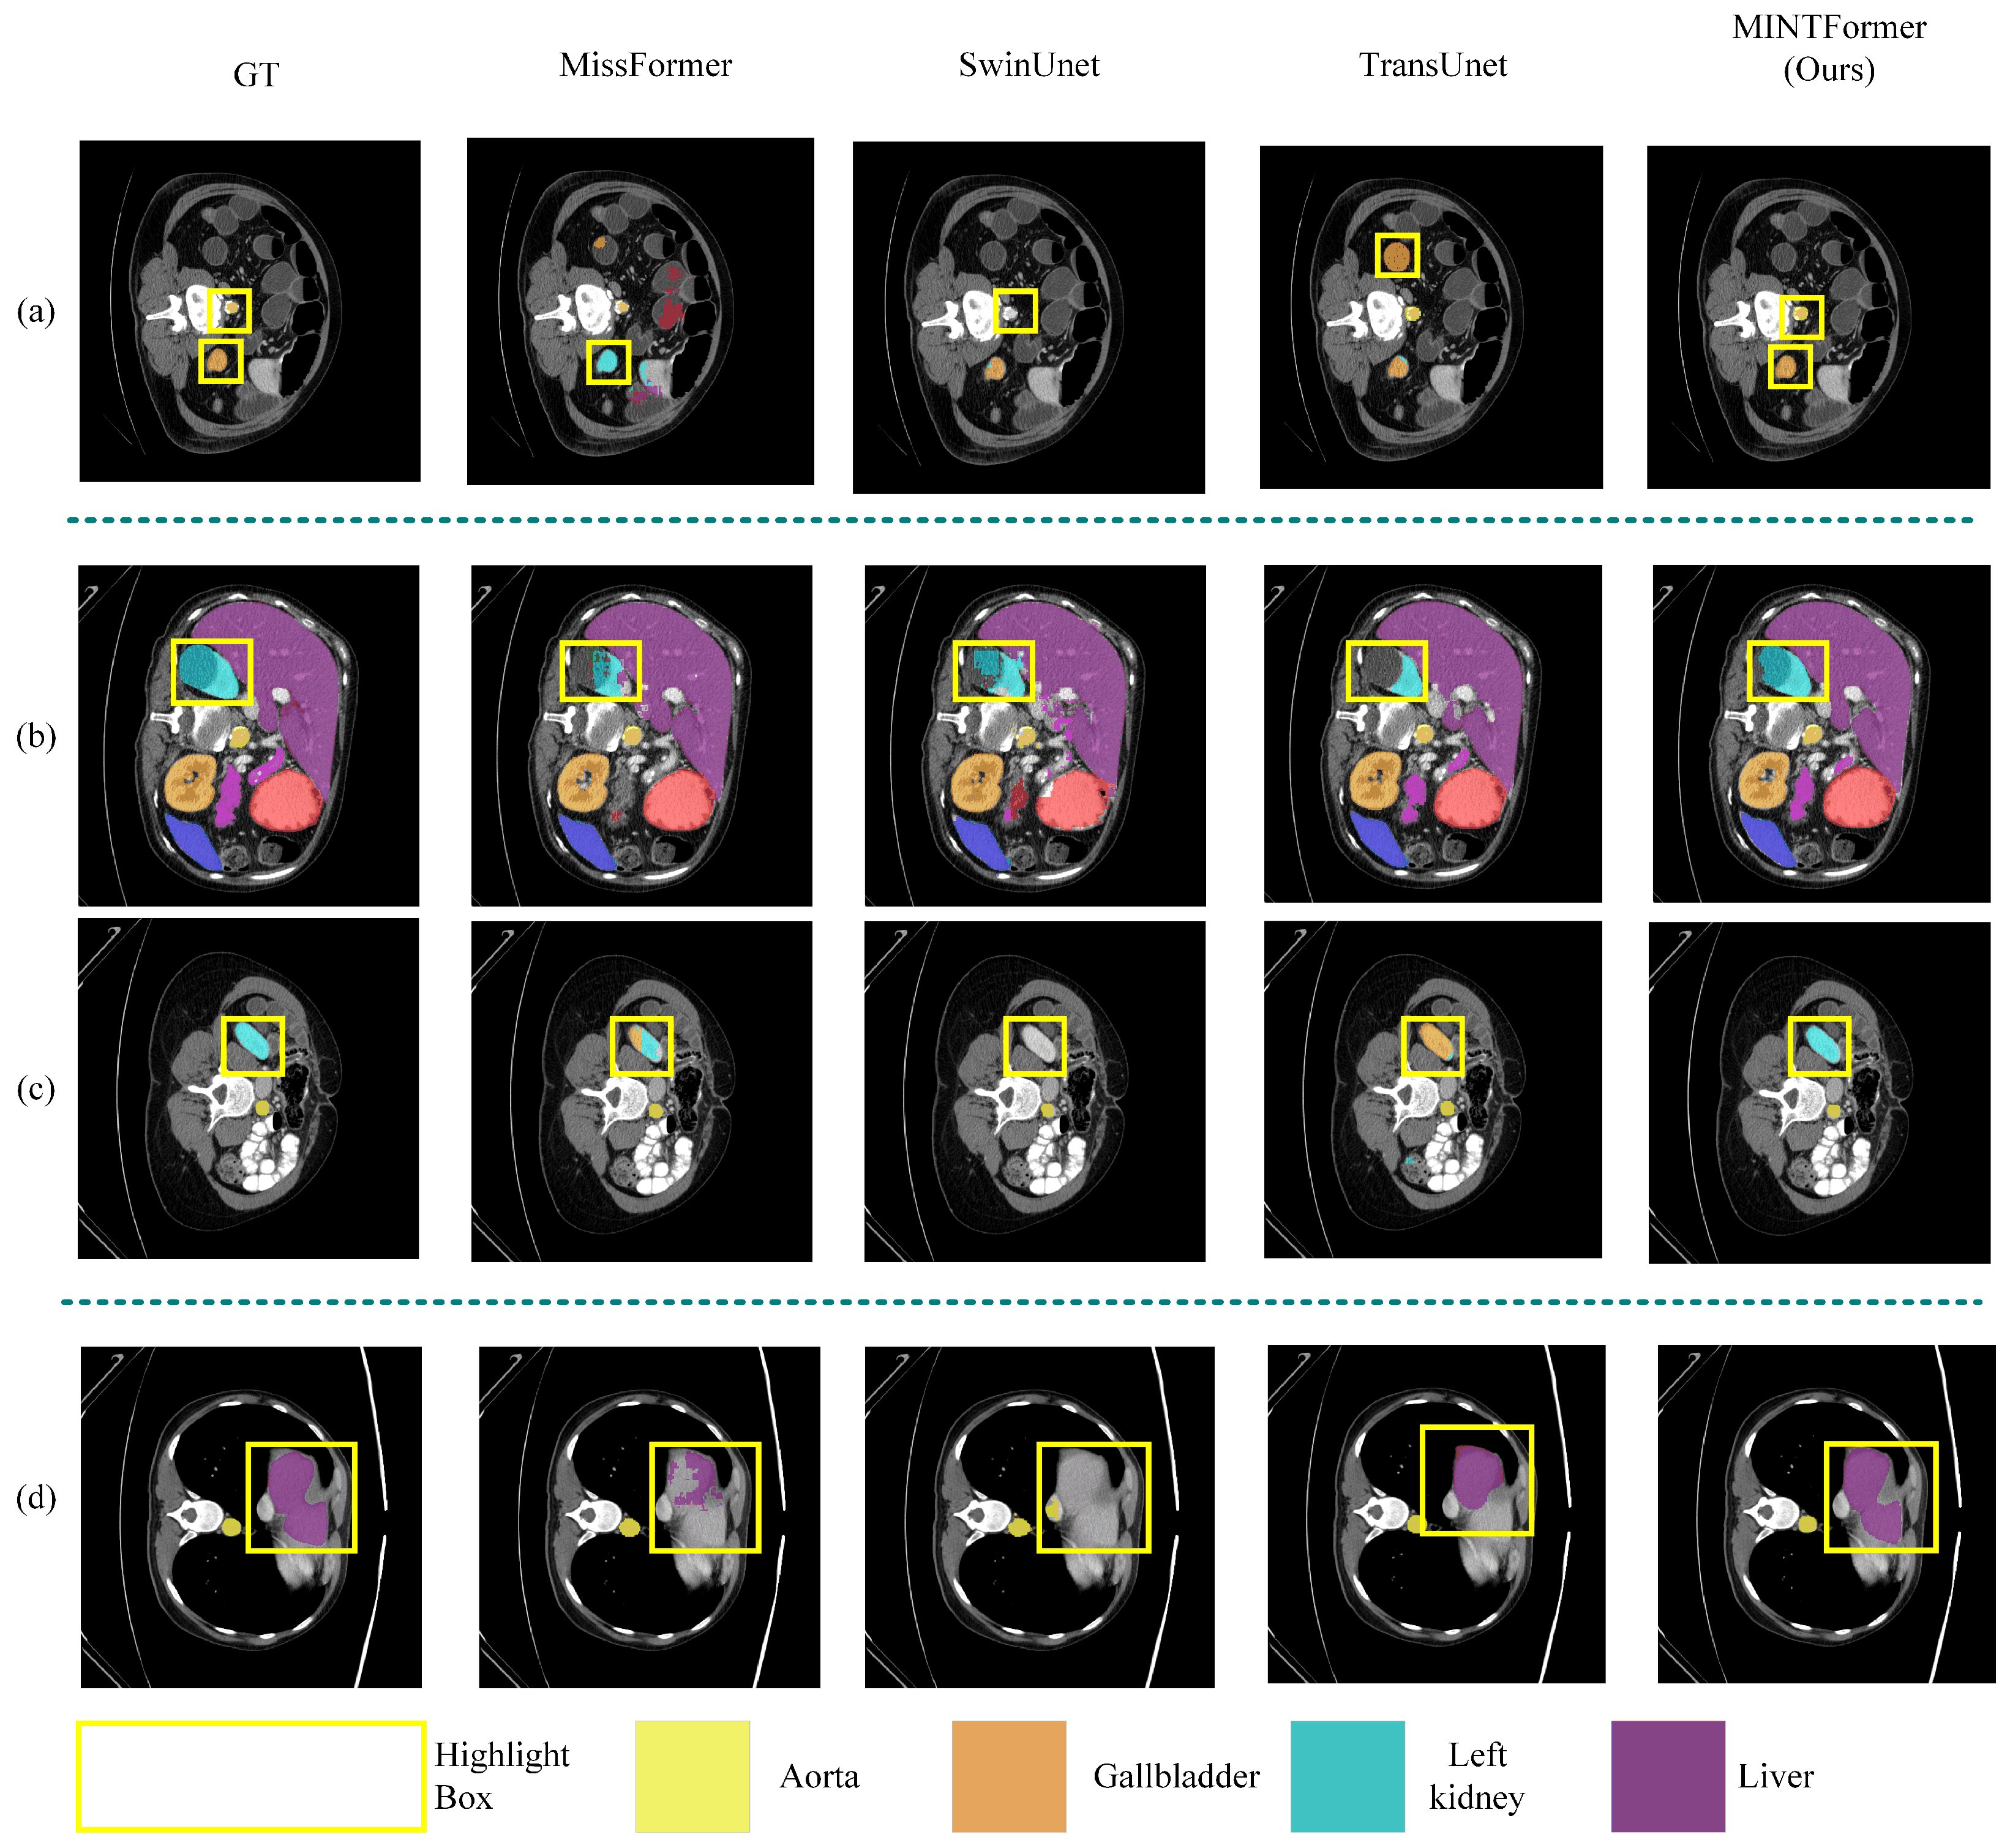

4.3.1. Experimental Results of Multi-Scale Organ Information Dataset

Synapse Dataset